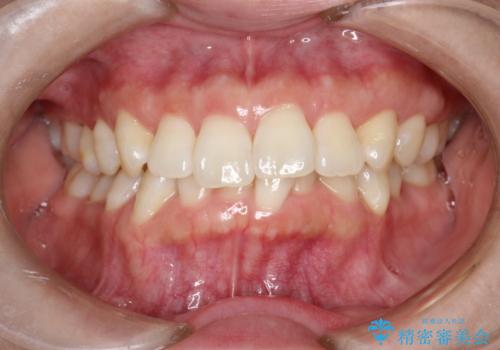

マウスピース枚数 初回33枚 +追加22枚 +追加31枚

概ね2年で治療完了しました。

マウスピース矯正の特性として動かすのが難しい歯を含むケースでしたが、当院独自の工夫を随所に盛り込み、狙い通りの治療結果が得られました。